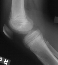

- XRAYS: No bony abnormalities noted on plain x-ray of the knee

Radiographic features:

- Benign appearing-- lesion is lytic, circular, and well circumscribed

with a sclerotic margin

- Malignant appearing-- bony cortex is eroded

V-- epiphyseal ; concentric radiolucency